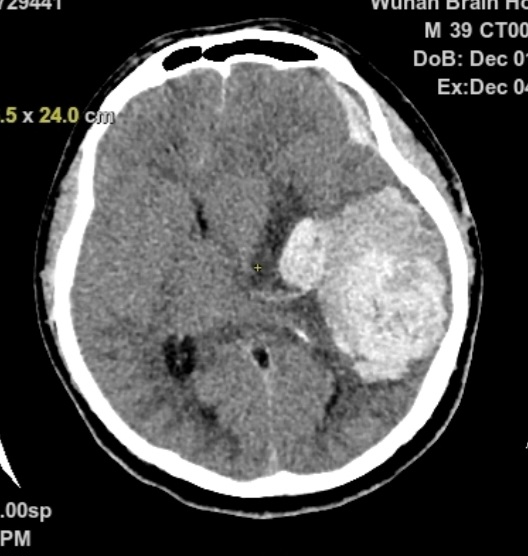

急诊头部CT显示左颞顶巨大脑内血肿,中线结构移位,脑疝

头部CTA提示:左颞顶AVM合并大脑中远端动脉瘤